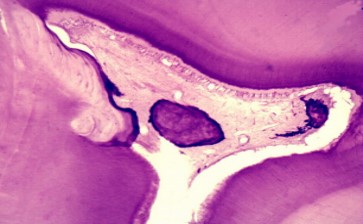

表现为髓室内的髓石(图8.2-2)和弥散于根管内的弥散性钙化两种类型。

图8.2-2 髓石